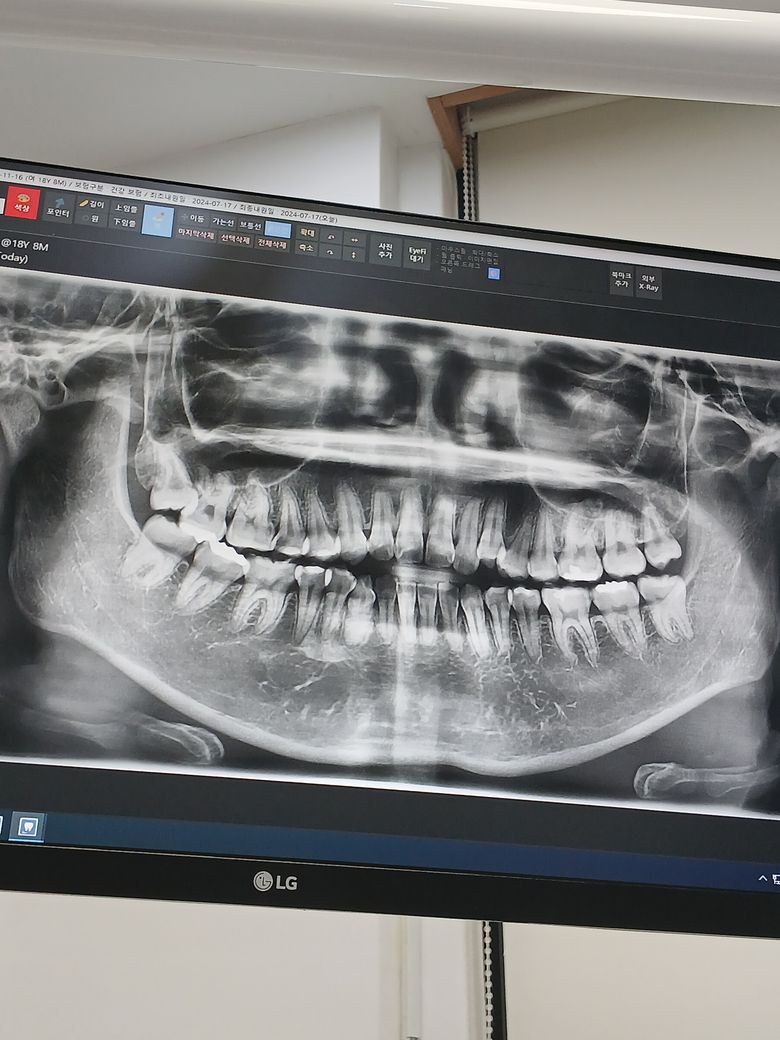

어느부분 충치가 있을까요? 부탁드립니다ㅜ

오늘 검진받았는데, 어느부분 어느정도 충치가 있는지 궁금해요ㅠㅠ 크라운 때울 게 몇개 된다고 하셨는데 정확히는 안알려주셔서...

충치 상태에 대해 정확히 알기 위해서는 파노라마 사진보다는 작은 방사선 사진(치근단사진)이 필요합니다. 파노라마 사진으로 보기에는 양쪽 위 두번째 작은 어금니 부위 충치가 의심됩니다.